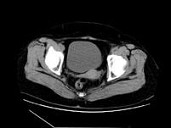

- 单项选择题女,27岁, 体检时B超发现右侧附件区囊性占位性病变,CT检查如图, 下列说法错误的是 ( )

A、病灶来源于右侧卵巢

B、病灶边界清晰

C、病灶为单房,壁薄,无分隔

D、考虑为卵巢浆液性囊腺瘤

E、考虑为卵巢囊肿